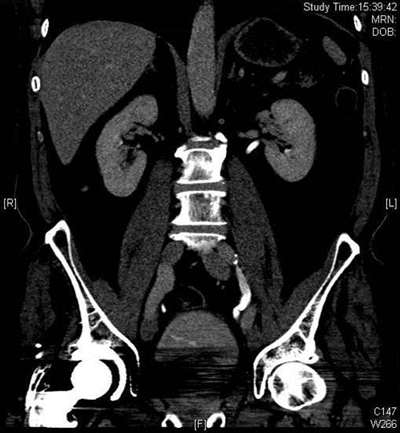

Figure 2a: Abdominal windows stone with contrast.

Figure 2b: Bone windows stone with contrast.

CT urograms can be performed with a pre-contrast CTKUB to assess for stone disease and calcification, but some centres only perform a post-contrast urographic phase in order to decrease radiation dose. Newer dual-energy CT scanners include software that enables a ‘virtual pre-contrast CT’ to be reconstructed by a subtraction technique. Using bone windows enables some calculi to be visualised even in the presence of contrast in the collecting systems due to the different HU values of contrast and calculi (Figure 2). However, it can be difficult to clearly depict some calculi using abdominal windows in this group of patients as the stone will be masked by the excreted contrast.